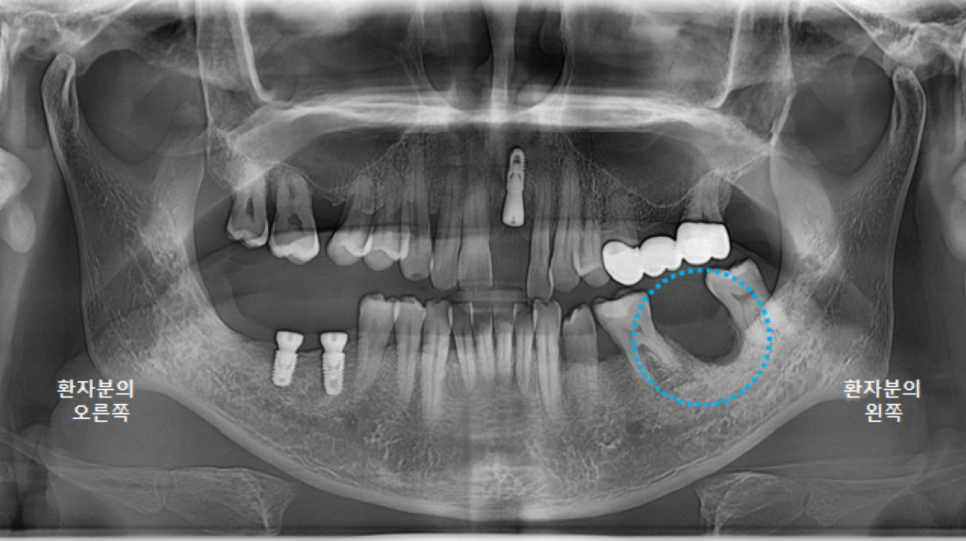

왼쪽아래 임플란트와 브릿지가 잘 마무리된 파노라마 엑스레이를 보실 수 있습니다.

자, 다시 왼쪽 위 임플란트를 살펴 볼까요?

왼쪽 위 상악동거상술과 임플란트 식립수술을 한 지 다섯달정도 지났습니다.

뼈의 두께가 얇아서 상악동거상술을 진행했고, 상악동에 염증이 있는 상태였습니다.

뼈이식을 충분히 했고, 뼈와 임플란트가 잘 유착될 수 있도록 충분히 기다렸습니다.

엑스레이상으로 고정이 잘 되어 보입니다.